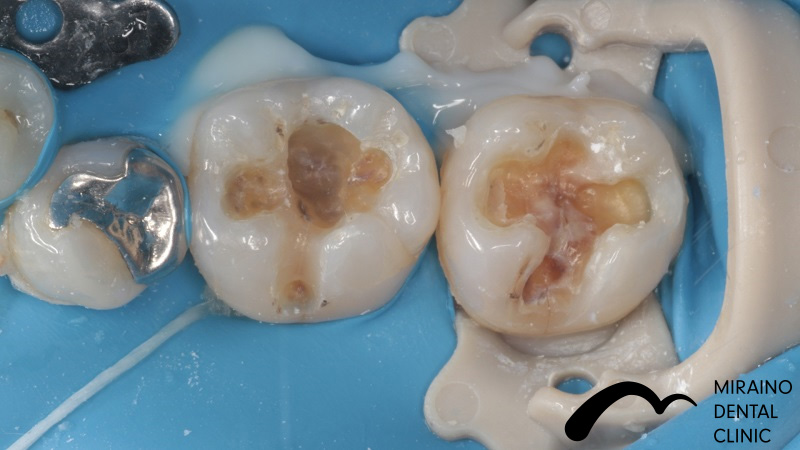

Case2

| 施術名 | 詰め物・メタルフリーインレー |

| 施術の概要 | 定期検診の際に、5年前以上に治療した銀歯に伱間があることを衛生士が見つけました。 沁みる、噛むと痛いといった症状はありませんでしたが、 次回再発した際は神経を取らないといけなくなる可能性が高いため、 なるべく再発しにくい歯科治療を希望され、メタルフリーインレーによる修復治療を行いました。 |

クリックして詳細を表示

| 施術の内容 | 銀歯は歯より硬すぎる、歯を腐食させる作用があることから約5年で再発すると言われています。 ラバーダムを用いて唾液による接着不良のリスクを排除し完全に水分を排除した状態でムシ歯治療を行います。 型取りを行い、技工士によって汚れの付きにくいセラミックで形を再現している。 |

| 1歯あたりの治療費 | 1歯:50,000円 |

| 考えられるリスク、副作用[全てにおいて] | 必ずしもご希望通りにならない事があります |

| 考えられるリスク、副作用[麻酔] | 麻酔を行う場合、腫れやむくみを生じる事があります。 |

| 考えられるリスク、副作用[噛み合わせ] | また、歯並びが変わる事により違和感を生じる事があります。 |

| 考えられるリスク、副作用[被せ・仮歯] | 強い衝撃を与えると、被せ物が欠けたり割れたり、外れたりする事があります。 |

| 考えられるリスク、副作用[根の治療] | 治療に際して、根の治療が必要になる場合があります。 |

| 考えられるリスク、副作用[根の治療・再発] | 被せ物をかぶせた後に根の病気が発症した場合、被せ物を外さなければならない事があります。 (外した被せ物の再利用は多くの場合、出来ません |

| 保証について | 治療後5年以内であれば再治療を行います。 喫煙、糖尿病、加齢、清掃不良など口腔衛生状態が不良な場合、ムシ歯の再発リスクになる事があります。 保証を受けるには当院にて年2回以上のメンテナンスが必要になります。 (メンテナンスは治療に関わらず、一般的にお口全体の衛生状態を維持するためには必要であると思われます。) |